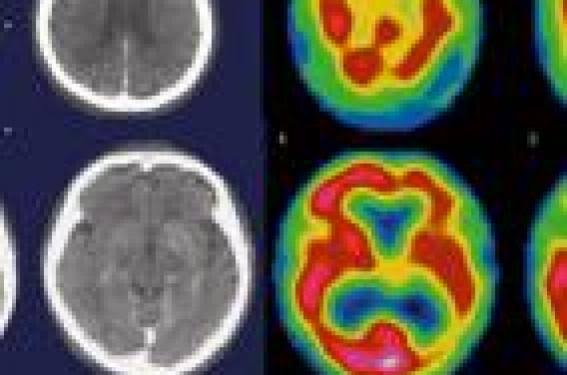

Une nouvelle étude publiée dans le Journal of Affective Disorders apporte un éclairage inédit sur les altérations cérébrales associées à la dépression chez les enfants et les adolescents. Intitulée « Magnetic resonance spectroscopy studies in children and adolescents with depression: A systematic review and meta-analysis », cette méta-analyse passe au crible les résultats de l’imagerie par résonance magnétique spectroscopique (IRM-S) pour mieux comprendre les mécanismes biologiques de cette pathologie chez les jeunes.

Les auteurs de cette revue systématique, menée sur 22 études totalisant 438 patients dépressifs et 388 témoins en bonne santé, se sont penchés sur la concentration de certains métabolites cérébraux. En ligne de mire : le N-acétyl-aspartate (NAA), marqueur de la santé neuronale, la choline, liée au métabolisme des membranes cellulaires, et le glutamate, principal neurotransmetteur excitateur du cerveau.

Les résultats révèlent une baisse significative du NAA dans le cortex préfrontal gauche des enfants et adolescents déprimés. Ce déficit pourrait refléter une altération du fonctionnement neuronal dans cette région du cerveau, largement impliquée dans la régulation de l’humeur, la prise de décision et le contrôle émotionnel. De plus, des réductions du glutamate et de la choline ont également été observées, bien que de manière moins homogène entre les études.

Ce profil biochimique contribue à l’objectivation de la dépression comme trouble neurologique et non seulement psychologique. Il suggère que des altérations cérébrales mesurables sont présentes dès l’adolescence, ce qui pourrait ouvrir la voie à des diagnostics plus précoces, voire à des traitements ciblés basés sur la neurochimie individuelle.

Cette étude marque néanmoins une avancée importante. Elle montre que l’IRM spectroscopique, en tant qu’outil non invasif, pourrait un jour devenir un allié précieux dans la détection et la prise en charge de la dépression chez les jeunes – une population encore trop souvent diagnostiquée tardivement, voire pas du tout.